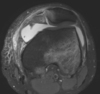

Patellar instability RF? anatomic factors? MPFL femoral origin-insertion? primary restraint in first? stability in deep flexion? exam: MPFL tenderness, +/- hemarthrosis, increased passive patellar translation can be measured how? what is the J sign? ## Footnote Clinical photograph with the knee in flexion (A) and in extension (B). The dotted line delineates the inverted “J” path taken by the patella

RF: ligamentous laxity, previous instability event, miserable malalignment " fem anterversion, genu valgum, ext tibial torsion, led to increased Q angle anatomic: patella alta (patella doesn't articulate w/ sulcus), trochlear dysplasia, excssive lateral patellar tilt, lateral femoral condyle hypoplasia muscle: dysplastic VMO, overpull of IT band and vastus lateralis **MPFL b/t medial epicondyle and duuctor tubercle, primary restraint in 1st 20-30 degrees of flexion** trochlear groove, patella height, and patellar tracking give stability in deep flexion. dynamic stability provided by **vastus medialis** patellar translation: normal less than 2, neutral is 0. lateral transtion of medial morder of patella to lateral edge of trochlear groove is consider 2 quadrants and is abnormal J sign: excessive lateral translation in extension which "pops" into groove as the patella engages the trochlea early in flexion associated with patella alta ## Footnote Schottle's point which can be reliably found radiographically just anterior to the posterior femoral cortex, and proximal to Blumensaat's line on a lateral radiograph. 1 mm anterior to a line extending from the posterior femoral cortex, 2.5 mm distal to the posterior origin of the femoral condyle, and proximal to Blumensaat's line, which is the anatomic femoral insertion of the medial patellofemoral ligament (MPFL).